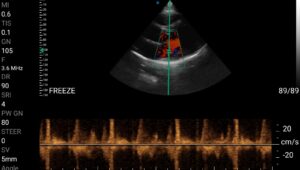

• Doppler καρδιακών βαλβίδων: Βασική εκτίμηση στένωσης/ανεπάρκειας.

Παραδείγματα

Ολες οι παραπάνω απεικονιστικές εξετάσεις έχουν ληφθεί από φορητή συσκευή όπως: Apple Iphone, Tablet, Samsung Mobile Phones και διάφορες άλλες φορητές συσκευές.

Παραδείγματα Video